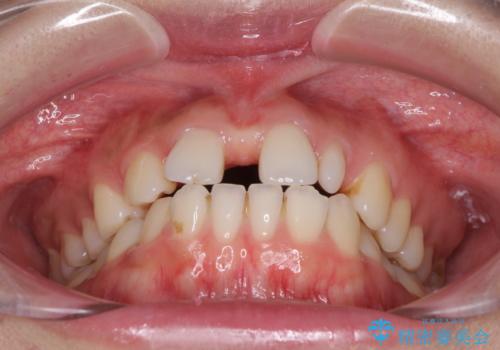

診察の結果、前歯が1本欠損しており、さらに矮小歯(通常よりも小さい歯)が1本存在していました。

欠損による前歯のスペースが大きかったため、事前にワイヤー矯正で前歯の位置を大きく動かし、その後は上下をインビザラインで整えることとしました。

前歯のスペースは、堅い線維の通った歯肉があり、幅も大きかったことから、歯肉切除を行った上でワイヤー矯正により移動を行いました。また、上唇小帯も歯間部付近まで付着していたため、合わせて切除しました。

ワイヤー矯正により、インビザラインよりも早く、歯軸の向きもコントロールしながら移動させることができました。